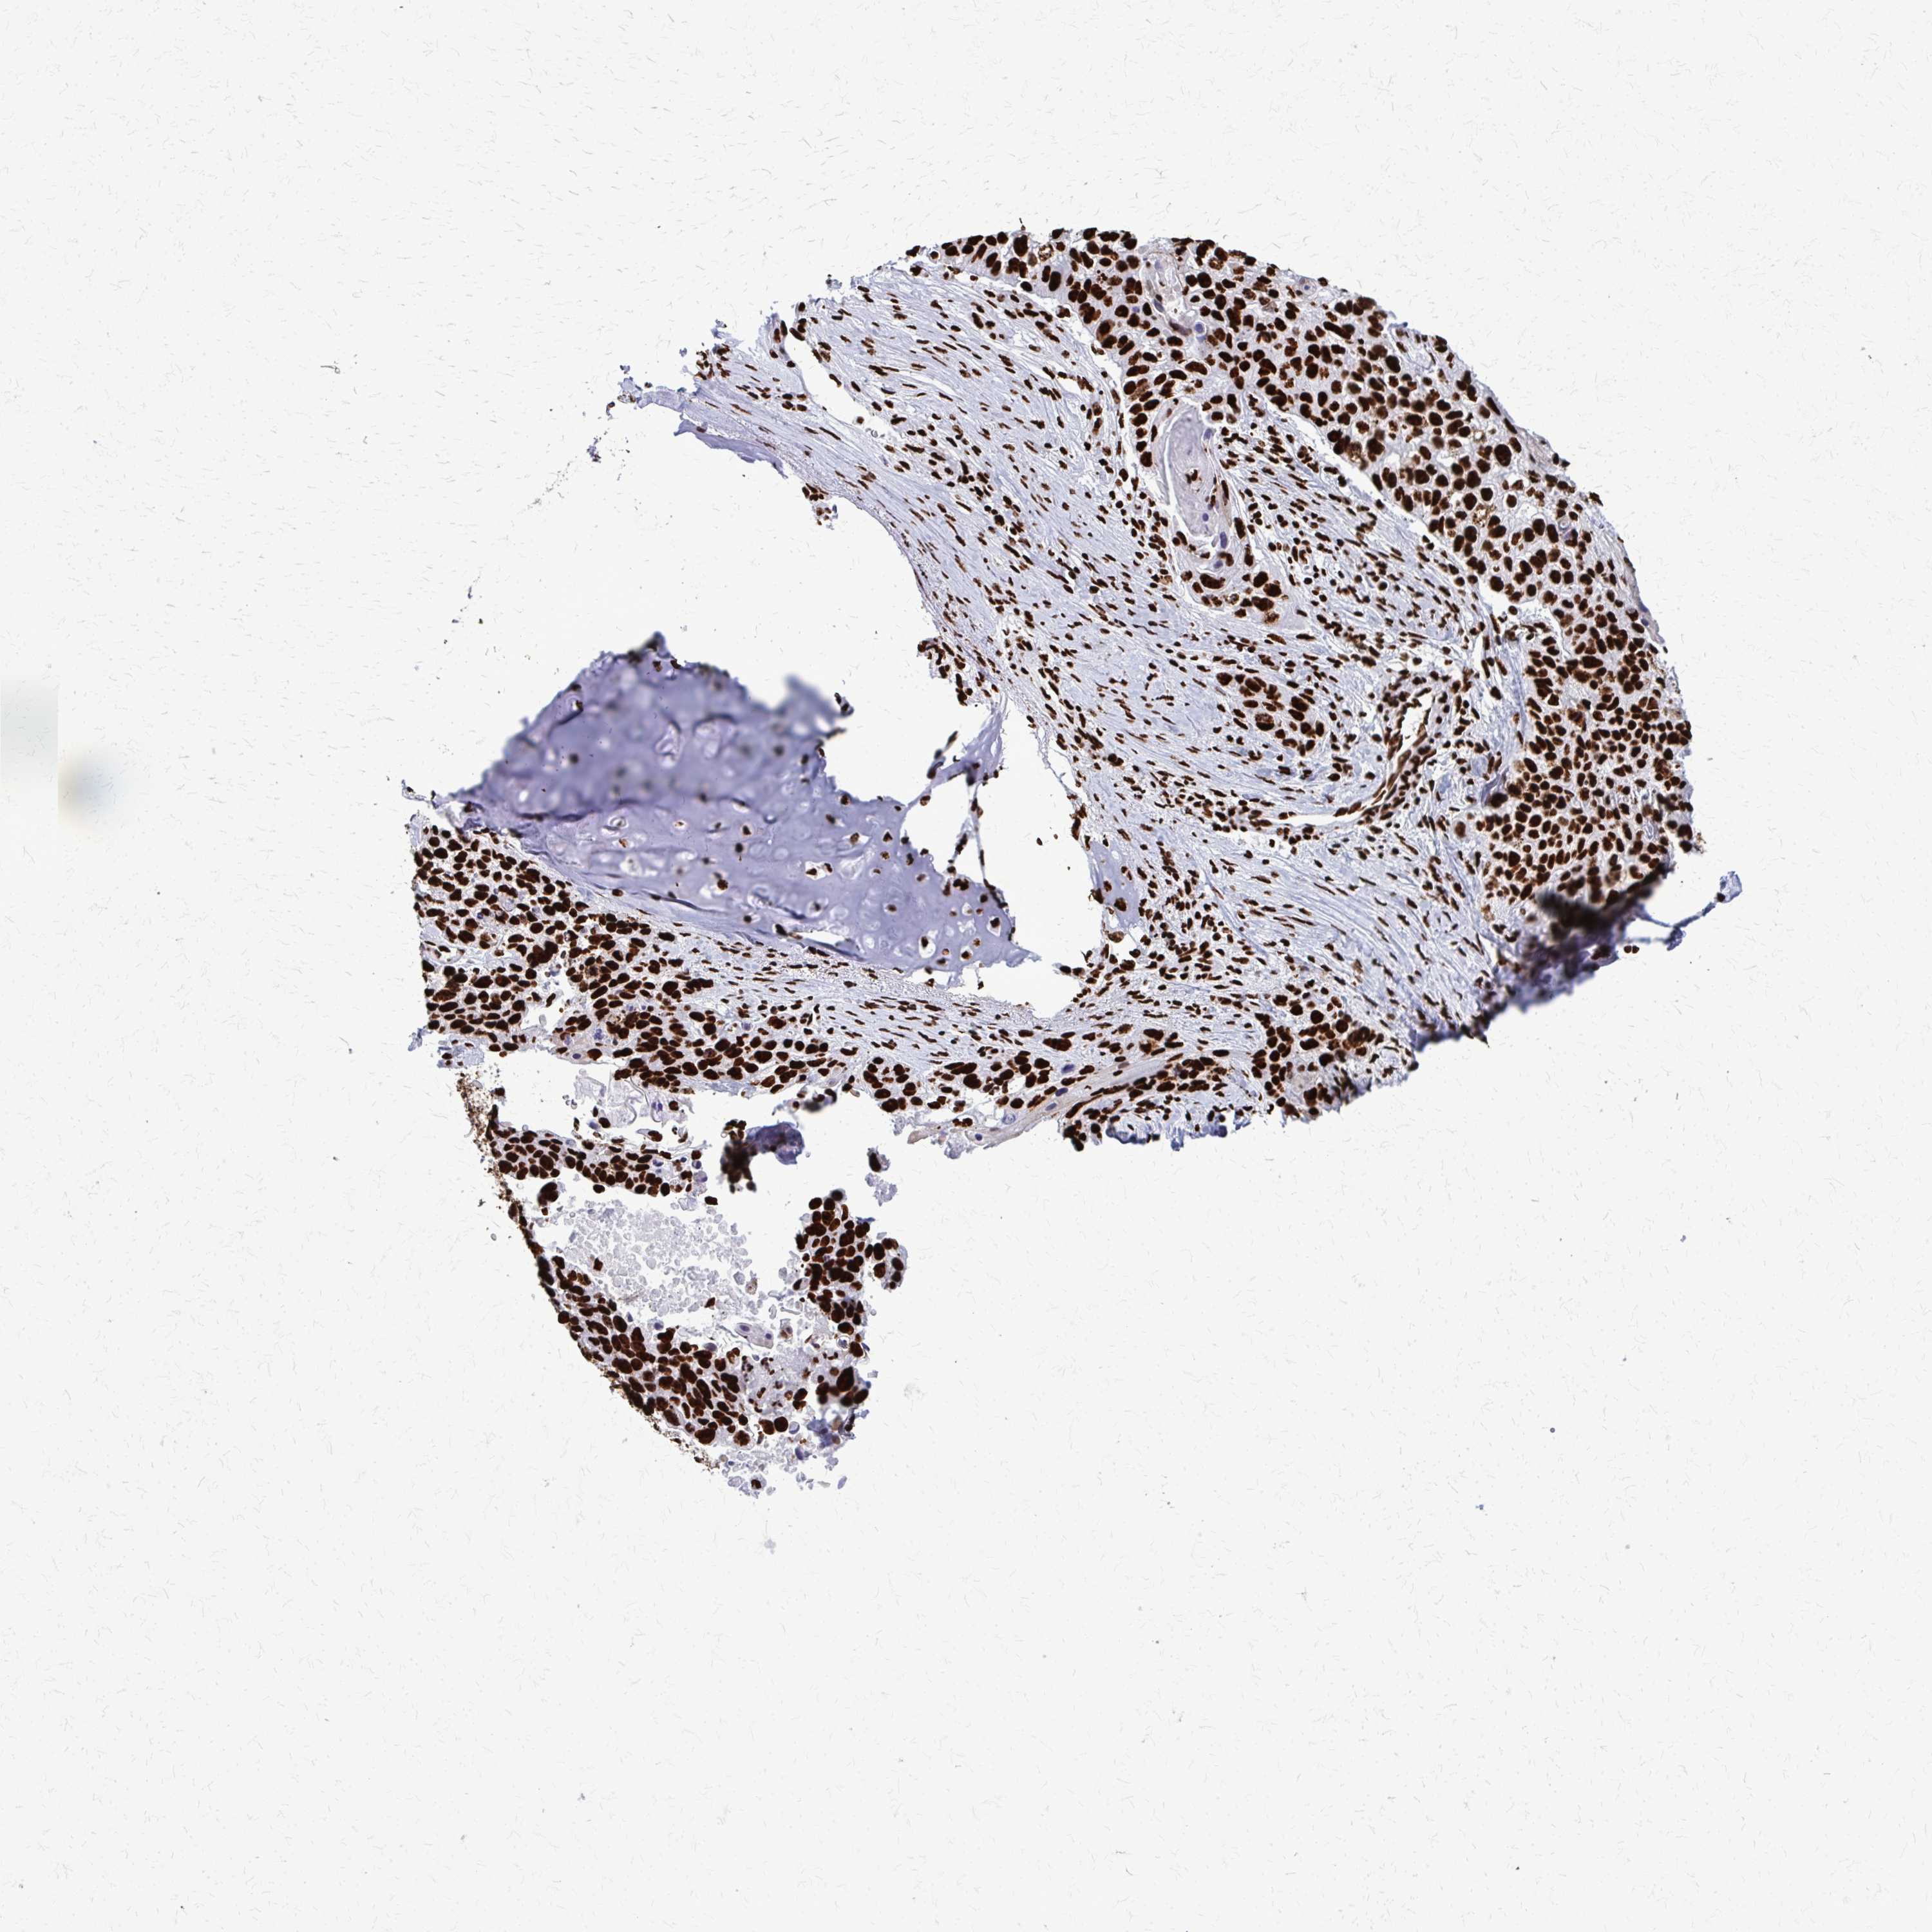

CANCER LUNG CANCER Show tissue menu

LUAD TCGA LUAD VALIDATION LUSC TCGA LUSC VALIDATION PROTEIN LUAD CPTAC PROTEIN LUSC CPTAC PROTEIN EXPRESSION

ANTIBODIES

AND

VALIDATION